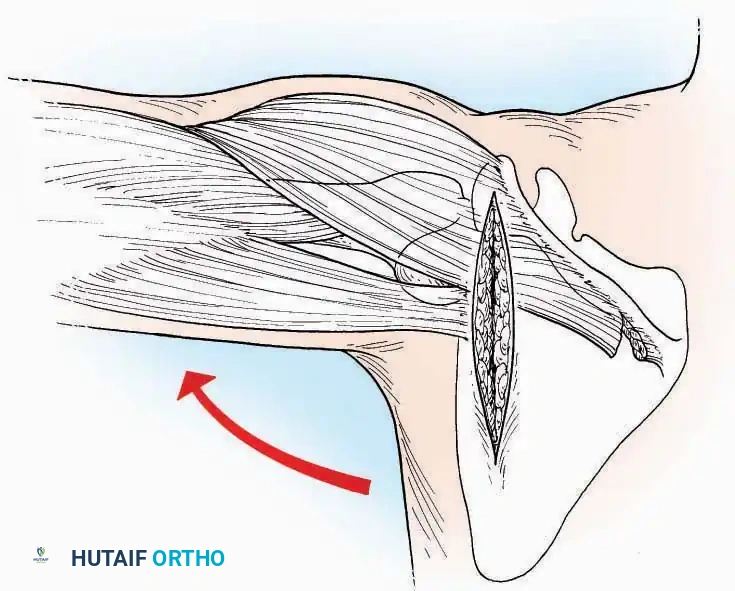

Kocher Approach (Curved L)

Indications: Complete excision of the calcaneus (calcanectomy) for malignant tumors or recalcitrant osteomyelitis.

Surgical Technique:

* Incision: Incise the skin over the medial border of the Achilles tendon, starting 7.5 cm proximal to the calcaneal tuberosity. Extend it distally to the inferoposterior aspect of the tuberosity, curve it transversely around the posterior heel, and continue distally along the lateral surface of the foot to the tuberosity of the fifth metatarsal.

* Deep Dissection: Divide the Achilles tendon directly at its insertion and carry the dissection down to the bone.

* Enucleation: To reach the superior surface, free all tissues beneath the severed Achilles tendon. The calcaneus can then be enucleated subperiosteally or extraperiosteally depending on the oncologic or infectious margins required.